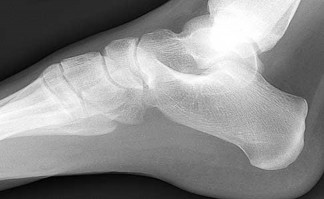

A 30-year-old female sustains a midfoot injury after falling from a horse. Radiographs demonstrate diastasis between the bases of the 1st and 2nd metatarsals. In a normal anatomic state, the native Lisfranc ligament originates and inserts on which two bony structures?

Explanation

The Lisfranc ligament is a stout, obliquely oriented intra-articular ligament that acts as the primary stabilizer of the second tarsometatarsal joint complex. It connects the lateral aspect of the medial cuneiform to the medial aspect of the base of the second metatarsal. Importantly, there is no direct ligamentous connection between the bases of the first and second metatarsals.